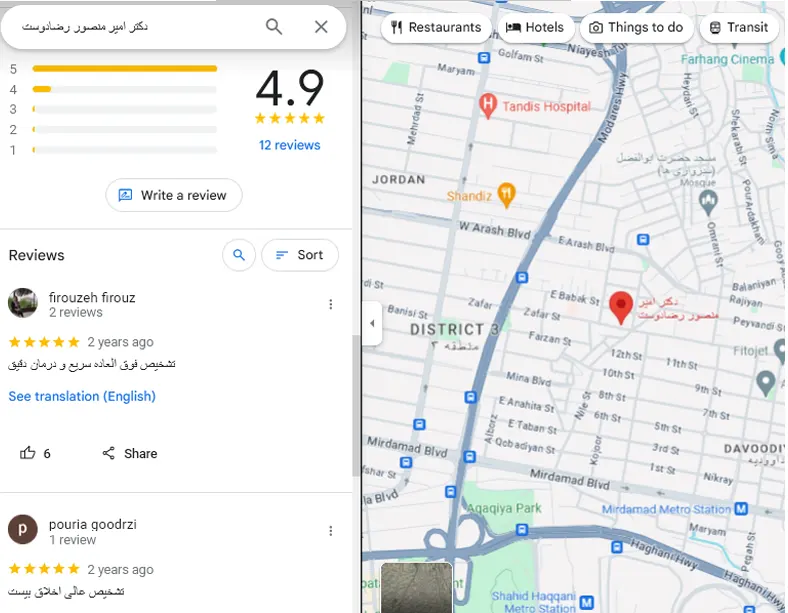

نمونه هایی از عمل جراحی بوتاکس معده توسط دکتر رضادوست برای بیماران داخلی و خارجی

این عمل جراحی هیچ دوره خاص و یا بستری بعد از عمل ندارد. مریض بعد از عمل می تواند تغذیه خود را شروع کند. اما توصیه ما این است که تا 24 ساعت بعد از عمل فقط مایعات خنک بنوشند. اثر بوتاکس معده از یک هفته بعد شروع می شود. تا سه ماه بوتاکس معده ماندگاری دارد. و هر 6 ماه یکبار قابل تکرار است.